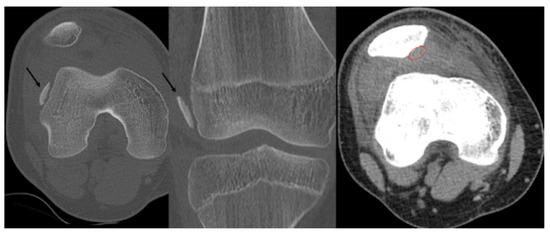

We investigated whether interrater reliabilities of the AO/OTA classification of patellar fracture change with the imaging modalities applied, including plain radiography and two- and three-dimensional (2-D and 3-D) computed tomography (CT). Seven orthopedic specialists and four orthopedic residents completed a survey of 50 [...] Read more.

We investigated whether interrater reliabilities of the AO/OTA classification of patellar fracture change with the imaging modalities applied, including plain radiography and two- and three-dimensional (2-D and 3-D) computed tomography (CT). Seven orthopedic specialists and four orthopedic residents completed a survey of 50 patellar fractures to classify the fractures according to the AO/OTA classification for patellar fractures. Initially, the survey was conducted using plain radiography only, then with 2-D CT introduced three weeks later and 3-D CT introduced six weeks later. Fleiss’ Kappa coefficients were calculated to determine interrater reliability. The overall interrater reliability of the AO/OTA classifications was 0.40 (95% CI, 0.38–0.42) with plain radiography only and 0.43 (95% CI, 0.41–0.45) with the addition of 2-D CT. With the addition of 3-D CT, the reliability was significantly improved to 0.54 (95% CI, 0.52–0.56). In specialists, interrater reliability of the classifications was moderate with all three imaging modalities. With the use of 3-D CT, interrater reliability of the classification was 0.53 (95% CI, 0.50–0.56), which was significantly higher than that with the use of 2-D CT (κ = 0.45; 95% CI, 0.42–0.48). In residents, interrater reliability of the classification was 0.30 (95% CI, 0.24–0.36) with plain radiography. The reliability improved to 0.49 (95% CI, 0.43–0.56) with the addition of 2-D CT, which was significantly higher than that with plain radiography only. The use of 3-D CT imaging improved interrater reliability of the classification. Therefore, surgeons, especially residents, may benefit from using 3-D CT imaging for classifying and planning the treatment of patellar fractures. Full article

Show Figures

Figure 1